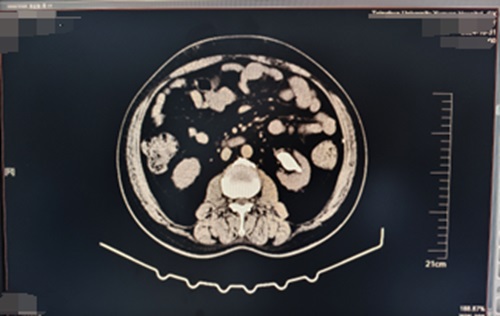

患者,男,61岁,主因“发现左肾鹿角形结石1月余”入院。泌尿系CT显示:左肾鹿角状结石;右肾结石。后在可控负压吸引下行输尿管软镜钬激光碎石术治疗肾结石。

术前示图如下: